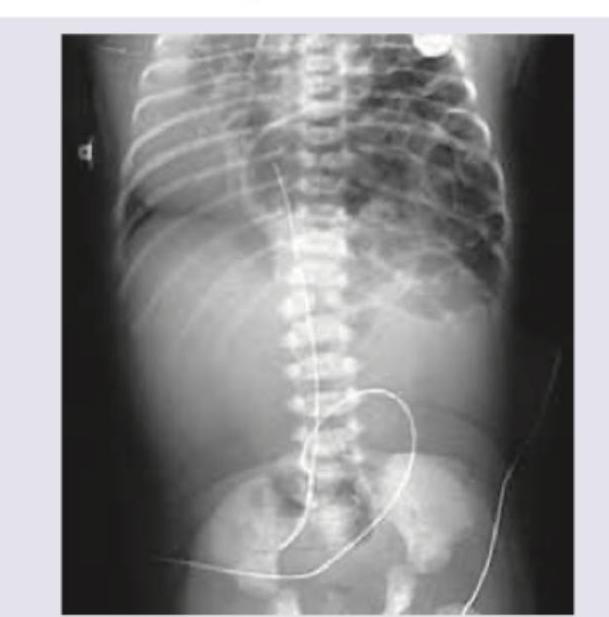

Identify the condition on the basis of infantogram shown in the image:

Explanation: ***Congenital diaphragmatic hernia*** - The infantogram shows loops of **bowel within the thoracic cavity**, displacing the heart and mediastinum. - This classic appearance, with visible **gas-filled loops** in the chest, is characteristic of a congenital diaphragmatic hernia, typically on the left side (Bochdalek hernia). *Cystic adenomatoid malformation* - This condition involves an abnormal growth of lung tissue forming **cysts**; these cysts typically appear as discrete radiolucencies or a solid mass within the lung. - Unlike in the image, it does not typically show distinct **bowel loops in the chest cavity**. *Pneumomediastinum* - This condition is characterized by air in the **mediastinum**, which would appear as lucency outlining the mediastinal structures, such as the heart and great vessels. - It does not involve the presence of **abdominal contents** within the chest cavity. *Congenital lobar emphysema* - This condition presents with **hyperinflation of a single lobe** (usually left upper lobe) causing mass effect and mediastinal shift. - It appears as a hyperlucent, overexpanded lobe, but does not show **bowel gas pattern** or abdominal contents in the thorax.